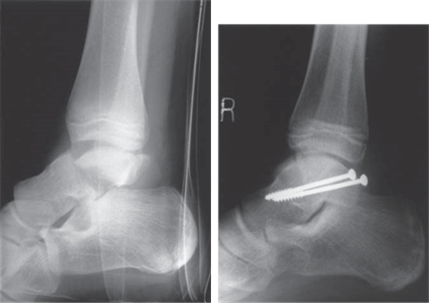

This patient was the driver in a high-speed RTA.

A B

Reproduced from C. Bulstrode et al., Oxford Textbook of Trauma and Orthopaedics second edition, 2011, fi gure 14.11.3, p. 1717, with permission from Oxford University Press.

What do you see in this picture and what causes this type of injury?

This is a lateral radiograph showing a displaced talar neck fracture. The subtalar joint appears to be incongruent. I would classify this with the Hawkinโ€™s system as a type II fracture.

T his injury is caused by the application of an axial load to the plantar aspect of the foot. This is a high-energy injury often associated with RTAs.

What is the standard treatment for this fracture?

T ype II and III fractures should be reduced and fi xed with two cannulated interfragmentary compression screws. I would use an antero-medial approach to the neck of the talus to openly reduce and fi x the fracture from anterior to posterior. My aim would be for anatomical reduction as mal-union is associated with poor results.

What complications should you anticipate in this patient?

E arly complications include compartment syndrome of the foot. There are a total of nine compartments in the foot. If necessary I would decompress the foot via two dorsal incisions, over the second and fourth metatarsals, and one medial incision.

Mid-term complications include infection, mal-/non-union, and AVN.

Long-term complications include osteoarthritis.

What is the probability of AVN in this case and what would you see?

Risk of AVN could be expected to be around 25 % in this case. I would expect to see increased density of the talar body followed by subchondral collapse and talar dome fragmentation.

I would also look for Hawkinโ€™s sign. This is the presence of subchondral lucency seen radiographically around 2 months after fracture. It is a good sign, indicating reperfusion of the talus.

Can you describe the blood supply to the talus?

The blood supply to the talus is via an anastomosis formed by three main arteries and their branches. The predominant supply to the body is from the posterior tibial via the branch to the tarsal canal. The talar head and neck are supplied by the dorsalis pedis and artery of the sinus tarsi, a branch of the peroneal artery.